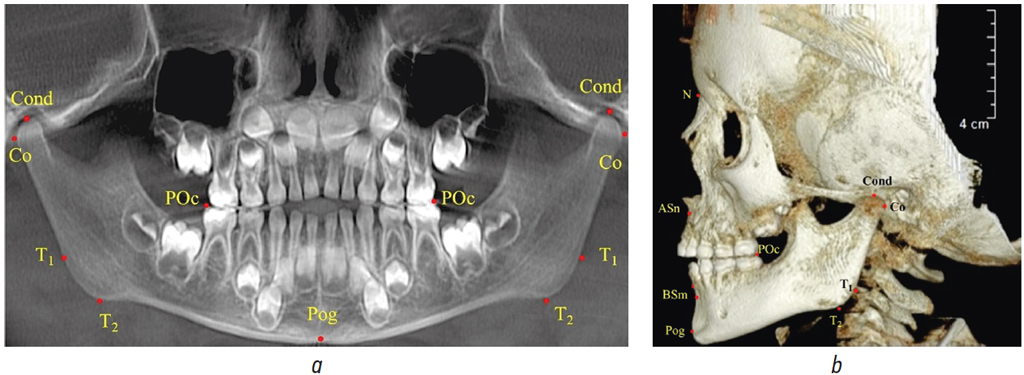

На ортопантомограмме общепринятыми точками каждой стороны были 2 суставные (Cond — на вершине суставной головки и Co — на задней точке выпуклости головки) и 2 точки выпуклости нижнечелюстного угла (Т1 — на ветви и Т2 — на теле нижней челюсти). Точка Pog (погонион) располагалась в нижней части шва нижней челюсти по срединной вертикали лица. Заднюю (постериальную) точку окклюзии (РOc) ставили на дистальном бугорке второго нижнего молочного моляра.

Измеряли расстояния между суставными и окклюзионными точками. Определяли угол нижней челюсти и расположение горизонтальных линий относительно друг друга. Вспомогательным методом исследования ортопантомограммы было построение суставного круга, центром которого была точка Cond, а диаметром служило отношение межсуставного расстояния Cond-Cond к коэффициенту 1,5 (рис. 1).

Рис. 1. Расположение основных точек на ортопантомограмме (а) и 3D-томограмме (b)

Fig. 1. Location of the main points on the orthopantomogram (a) and 3D tomogram (b)